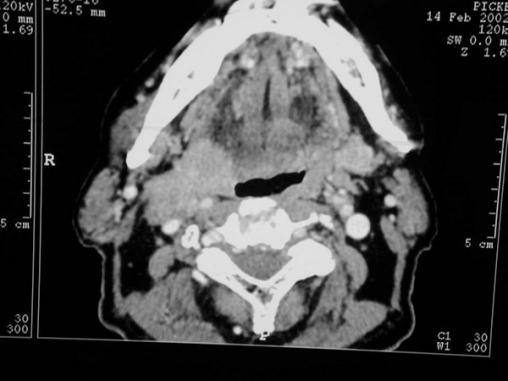

Tumeur de la paroi latérale droite de l’oropharynx

Coupe scanner axiale montrant une tumeur de la paroi latérale droite de l’oropharynx.